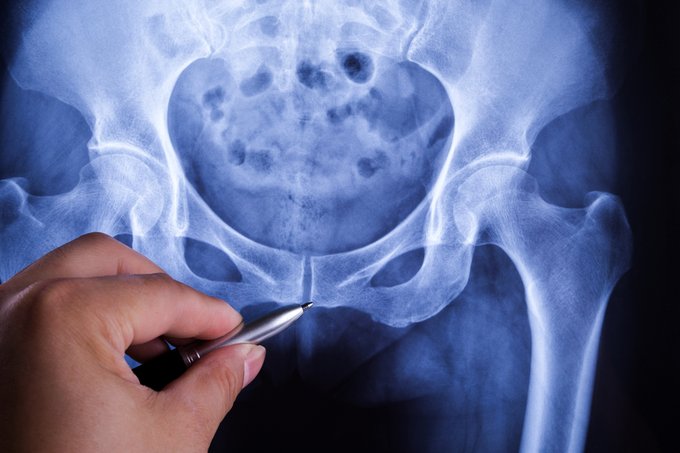

¿Por qué a veces duele la pelvis? Entérate aquí ow.ly/D6wm50xjFAB